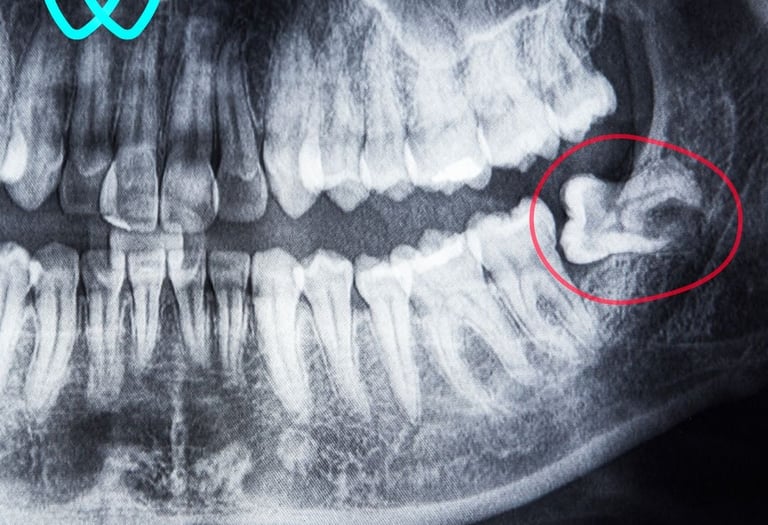

Realizamos procedimientos como extracciones quirúrgicas de terceros molares retenidos, regularización de rebordes óseos, fenestración de caninos, biopsias de lesiones orales, entre otros. Contamos con especialistas entrenados en técnicas mínimamente invasivas, anestesia local o sedación según el caso, y protocolos de bioseguridad rigurosos. Nuestro enfoque combina precisión clínica, control del dolor y una recuperación rápida para nuestros pacientes.

Cirugía maxilofacial